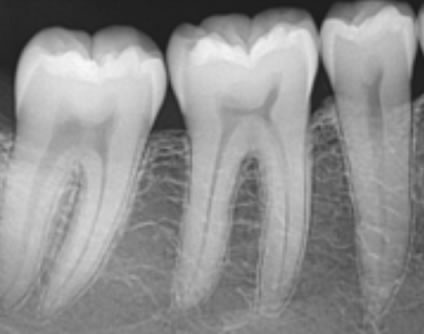

Pojedinačna snimka zuba - (intraoralna snimka) - Snimka prikazuje detaljnije i preciznije stanje zuba i okolne kosti.

Koristimo je uvijek za precizniju dijagnostiku patoloških stanja zuba i okolne kosti te nakon liječenja zuba.